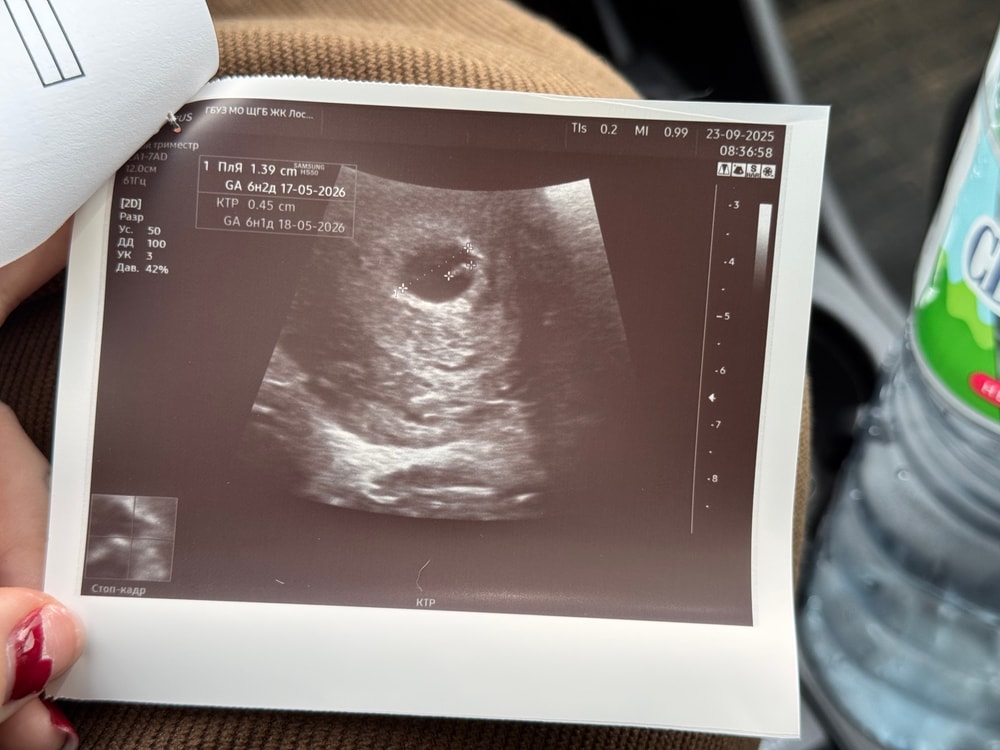

итого: 14.09 плодное яйцо - 3мм, 23.09 плодное яйцо - 13,9мм!!😍 ктр 0,45